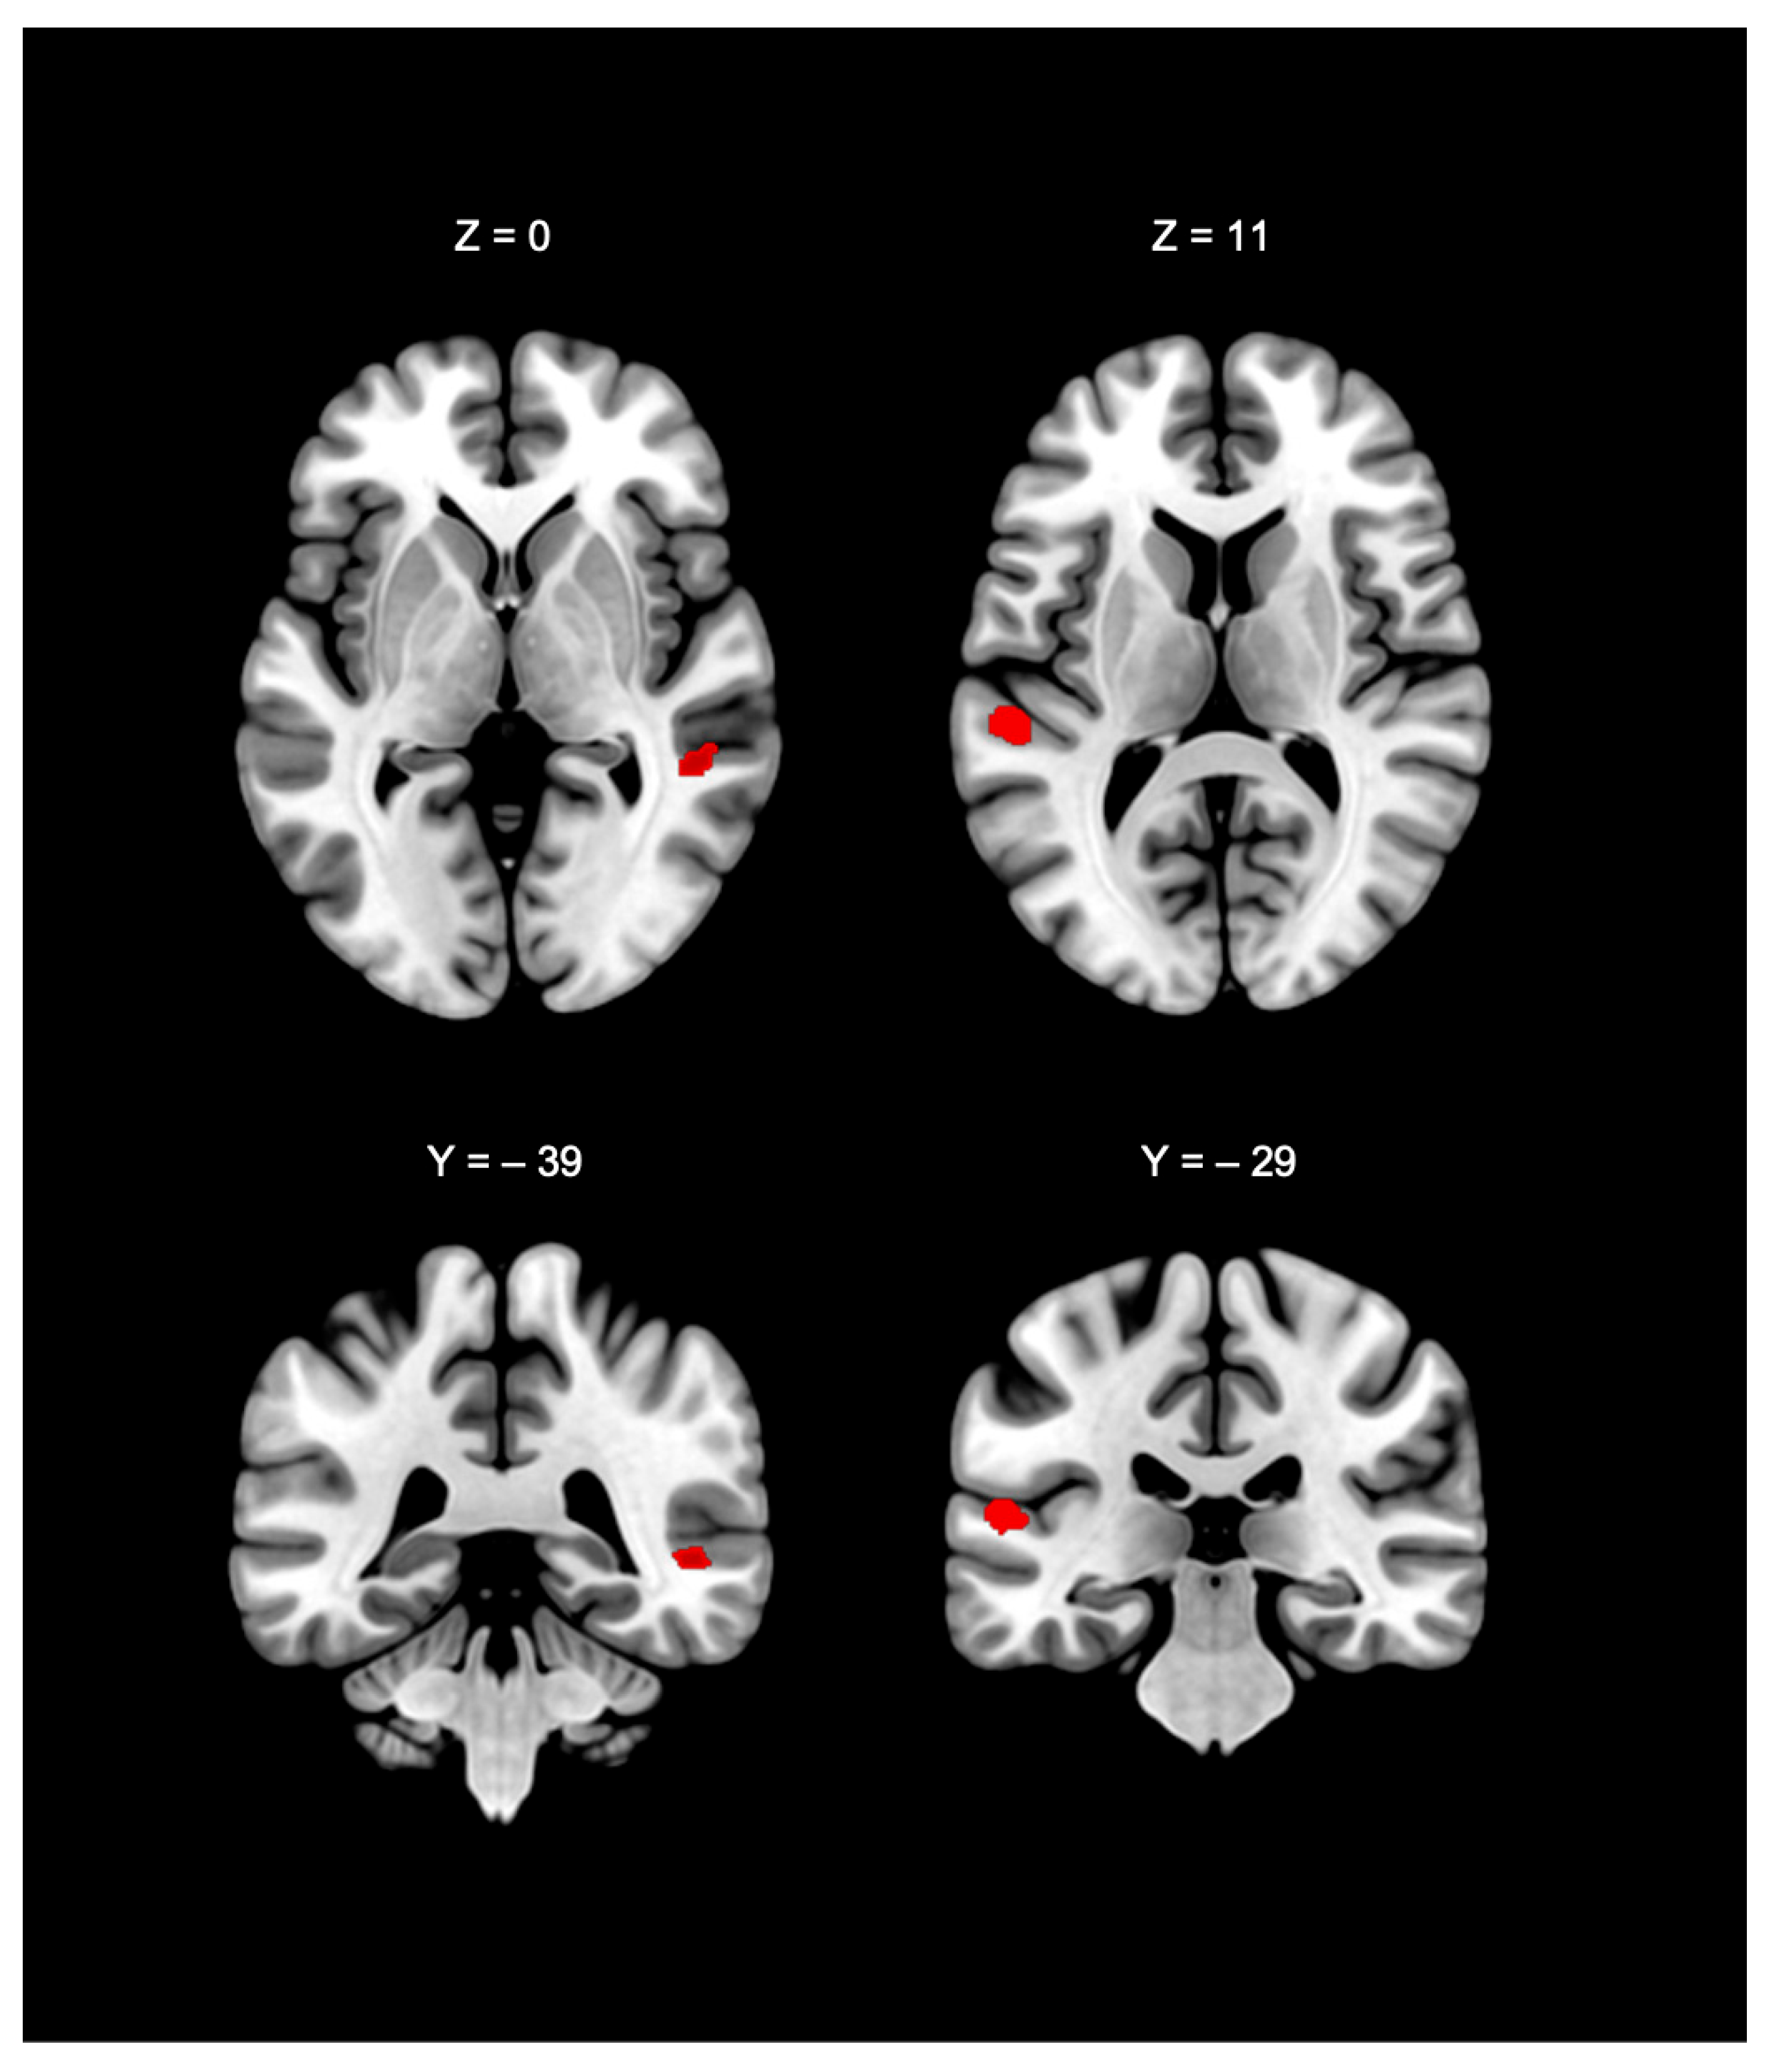

| Cluster # | Cluster Size | Anatomical Area | p Value | z-Score | MNI Coordinates (x, y, z) | ||

|---|---|---|---|---|---|---|---|

| 1 | 584 mm3 | Left superior temporal gyrus, BA41 | 0.0159 | 2.15 | −56 | −32 | 12 |

| Left superior temporal gyrus, BA41 | 0.0178 | 2.1 | −54 | −28 | 10 | ||

| 2 | 192 mm3 | Right middle temporal gyrus, BA21 | 0.0167 | 2.09 | 52 | −38 | 2 |